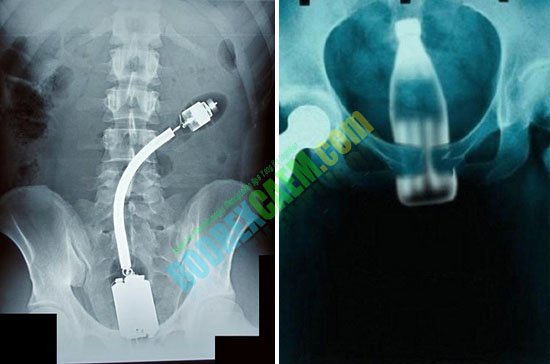

Contoh beberapa foto sinar X di bawah ini, beberap orang mencoba memasukkan benda-benda asing kedalam tubuhnya dan yang terjadi tidak seperti yang dia bayangkan.

Coba perhatikan dengan seksama benda-benda dalam hasil foto sinar x dibawah ini. Dimasukkan ke dalam tubuh lewat mana benda benda tersebut? Saya yakin anda semua akan menemukan jawabannya.